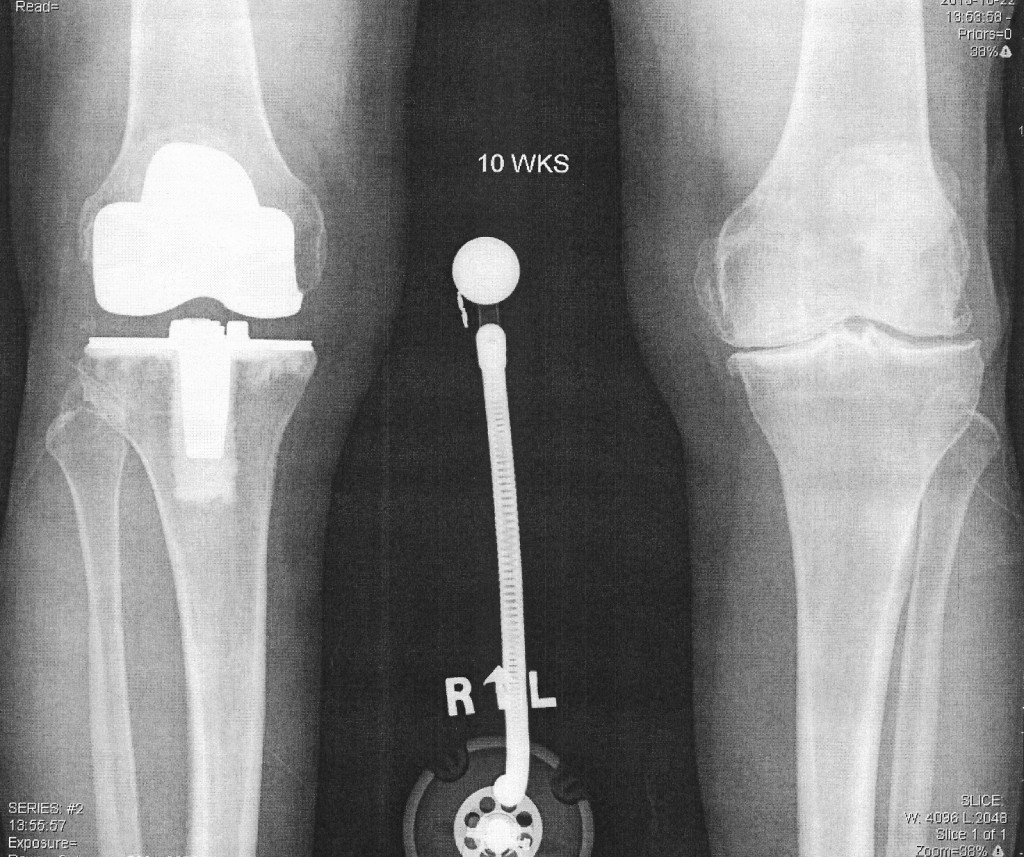

Knee Replacement Surgery & Makoplasty How Much Are Knee Worth As to knee injuries, you’ll likely see a settlement amount above the average when surgery is required to repair the injury. After severe knee injuries, will a company have to pay for their worker's full knee replacement surgery? Learn what factors determine the value of your knee injury insurance claim or lawsuit. Compensation values can range from $10,000. Mild knee. How Much Are Knee Worth.

From www.scottsdalejointcenter.com

kneereplacementxray The Orthopedic & Sports Medicine Institute in How Much Are Knee Worth Mild knee injuries won’t receive as much settlement money, while employees whose wounds require surgery or a complete knee. Compensation values can range from $10,000. Severe knee and leg injuries typically require surgery, intense therapy, and a long recovery. When surgery is required for a torn anterior cruciate ligament. Learn what factors determine the value of your knee injury insurance. How Much Are Knee Worth.